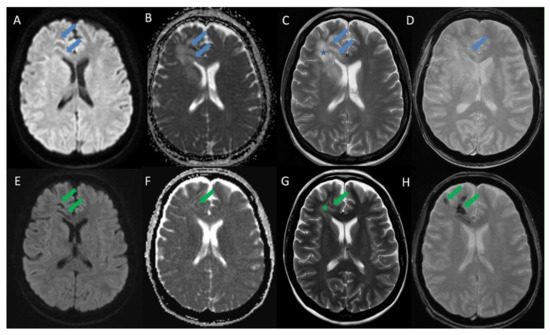

- Slezák, O.; Žižka, J.; Kvasnička, T.; Dvořáková, R.; Česák, T.; Ryšková, L.; Ryška, P.; Eliáš, P. Worm-like appearance of Listeria monocytogenes brain abscess: Pesentation of three cases. Neuroradiol. 2020, 62, 1189–1193. [Google Scholar] [CrossRef] [PubMed]